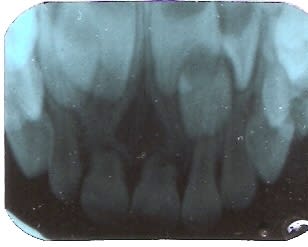

J'envoie une radio où l'odontome se voit bien.

Le petit a vu un spécialiste : pas de kyste, dent surnuméraire à surveiller pas d'intervention pour l'instant. Merci pour vos réponses

Numériser0002 cyclol - Eugenol

pr le kyste,je pense qu'on est ts d'accord depuis le debut:pas de kyste

maintenant pr les surnuméraires il semble qu'il y en ait une? mais là aussi on est d'accord:une PANO stp et pr le moment tu ne touches à rien

wait and see...